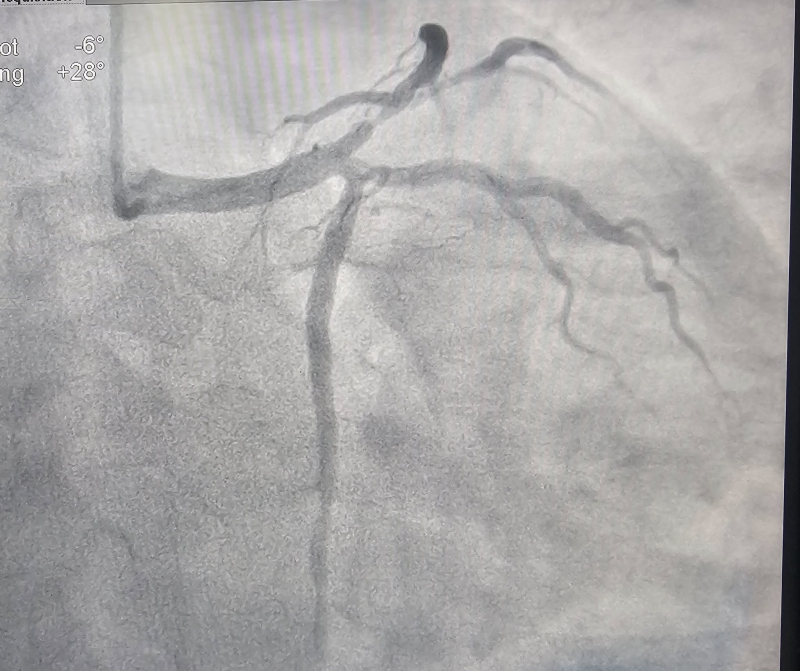

Các bác sĩ Khoa Tim mạch – Bệnh viện Bãi Cháy vừa can thiệp thành công cho bệnh nhân nam 34 tuổi bị nhồi máu cơ tim cấp. Kết quả chụp mạch vành cho thấy bệnh nhân hẹp 90% động mạch liên thất trước (LAD) và nhánh chéo 1 (Diag1). Người bệnh được xử trí kịp thời bằng kỹ thuật can thiệp đặt stent chỗ chia đôi (Mini-Crush), tái thông dòng chảy mạch vành, giúp bảo toàn chức năng tim.

Hình ảnh: trước và sau khi can thiệp